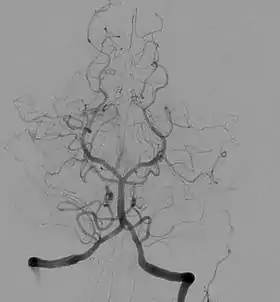

![]() Angiogram of the brain showing a transverse projection of the vertebro basilar and posterior cerebral circulation. | |

Cerebral angiography provides images of blood vessels in and around the brain to detect abnormalities, including arteriovenous malformations and aneurysms.[5] One common cerebral angiographic procedure is neuro-vascular digital subtraction angiography.[6][7]